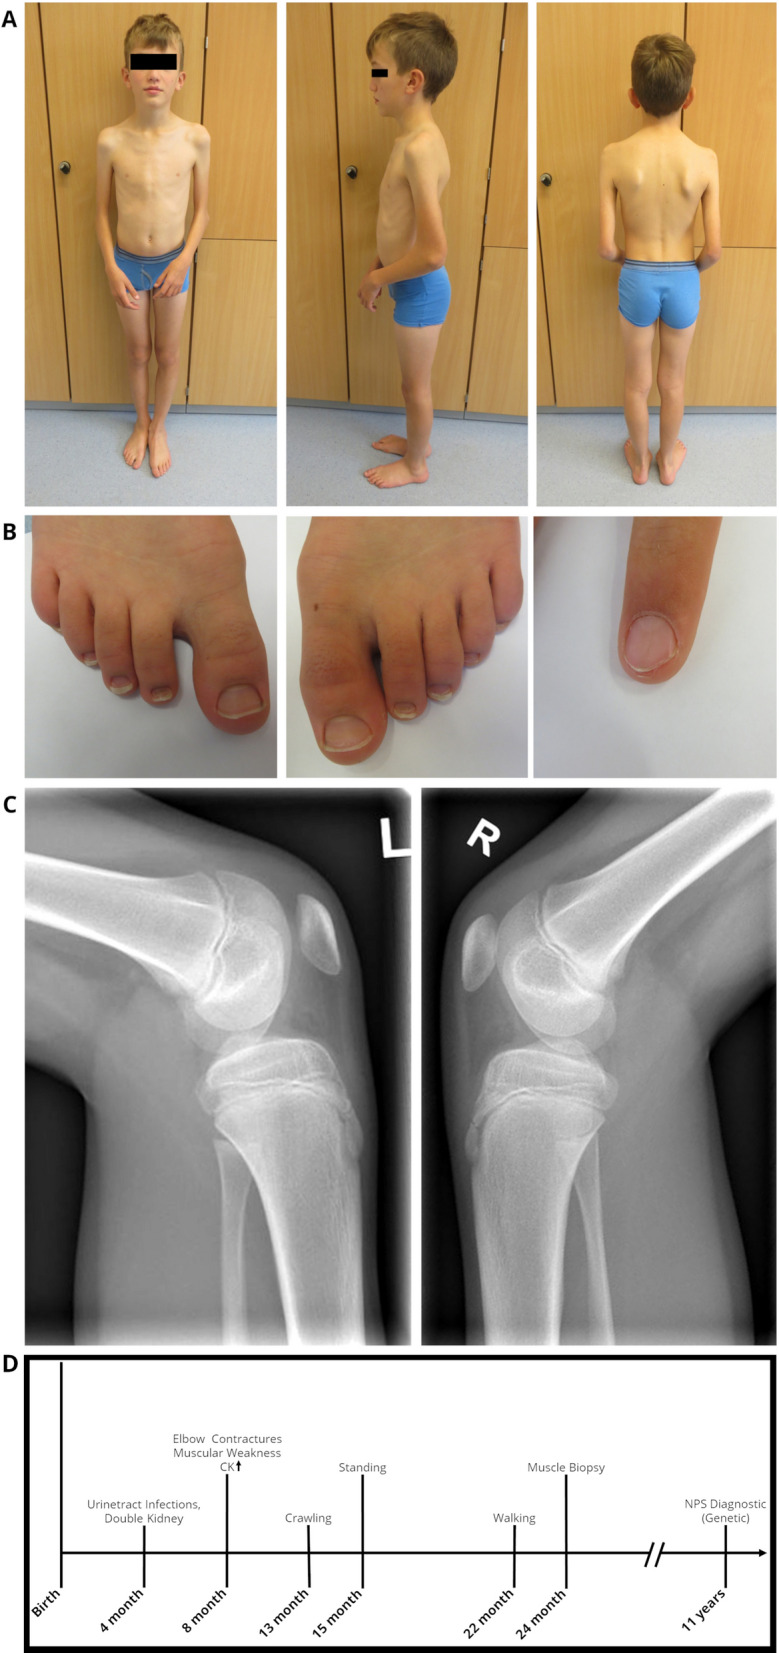

Further neuropediatric follow-up examinations revealed constant muscle weakness of the upper extremities, scapulae alatae and mild motor developmental delays with myalgias (Fig. 1A). The index finger of the left hand showed a triangular lunula but no dystrophic signs (Fig. 1B). Physiotherapy and ergotherapy occur as supporting therapy—mild improvements of the contractures have been shown.

Fig. 1.

Clinical findings in our index. At the age of 12 years: A Pronounced elbow contractures on both sides, with atrophy of the upper arm muscles and scapulae alatae, B mild dystrophic nails of the feet and triangular lunula of the finger nail, C Patellar hypoplasia on both sides. D Schematic representation of the diagnostic work-up along with clinical findings in our NPS patient